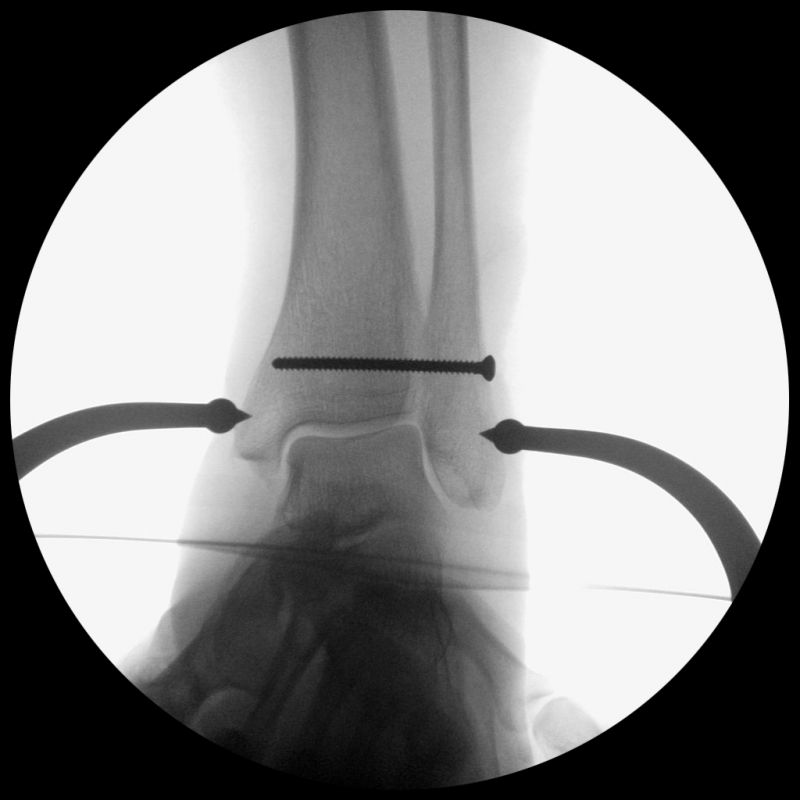

Die eigentliche Reposition der Syndesmose erfolgt mittels einer Repositionszange über dem Malleolus medialis und lateralis, entlang der Achse des oberen Sprunggelenkes und wird nach Reposition in anatomischer Stellung fixiert 52. Dabei ist auf eine Neutralstellung im oberen Sprunggelenk zu achten. Die temporäre Fixierung des DTFG kann mittels Schraube(n) oder einem dynamischen System (Suture Button - z.B. Tight-Rope, Fa. Arthrex™) erfolgen. Bei der Fixierung mittels Schraube können eine oder zwei Schrauben von 3,5-4,5 mm Stärke, tri- oder quadricortical, verwendet werden 53. Dies werden am posterolateralen Rand der Fibula in leicht aufsteigender Technik (30°), circa 2 cm und 3,5 cm oberhalb der tibiotalaren Gelenkfläche, parallel zur OSG-Achse nach entsprechendem Vorbohren eingebracht. Eine Schraubenpositionierung 2 cm oberhalb der tibiotalaren Gelenkfläche konnte in biomechanischen Untersuchungen eine bessere biomechanische Stabilität des DTFG gewährleisten als eine Positionierung der Schraube weiter proximal 54. Keinen Vorteil gegenüber tricortical eingebrachten Stellschrauben wiesen dagegen Schrauben auf, welche vier Corticalices fassen 55. Ob eine Entfernung der Syndesmosenstellschraube sinnvoll ist oder nicht, ist bist heute Bestandteil der internationalen Diskussion 56. Wir Entfernen Stellschrauben nach ca. 6 Wochen bei erhaltenem PITFL, sind alle Syndesmosenbänder verletzt, wird die Stellschraube 8 Wochen belassen.

Alternativ können verschiedene dynamische Systeme verwendet werden. Hierbei erfolgt, wie oben beschrieben, die Reposition der DTFG mittels Repositionszange. Anschließend wird in derselben Technik, wie bei der Syndesmosenstellschraube, quadricortical vorgebohrt. Hierauf wird durch den vorgebohrten Tunnel das Fadensystem (Suture-Button) von lateral nach medial durchgezogen und medial transkutan über die an dem Fadenende befestigte Nadel ausgeleitet. Über das speziell angebrachte Fadensystem lässt sich der mediale Button parallel zur medialen Kortikalis ausrichten und durch Zug am lateralen Faden an die medialen Tibiakortikalis heranzuiehen. Anschließend wird durch Anspannen der lateralen Fadenenden der laterale Button auf der Fibula platziert. Nach Erreichen der gewünschten Festigkeit und Reposition des DTFG werden die lateralen Fadenenden verknotet und abgeschnitten. Die medialen Fadenenden werden ebenfalls entfernt. Ziel des dynamischen Stabilisierungsverfahren ist eine physiologische Bewegung im DTFG zu ermöglichen bei gleichzeitiger Sicherung der Gelenkstabilität 57. Eine Materialentfernung ist bei diesen Systemen nicht zwingend erforderlich. Bei der ersten Generation der Suture-Button-Systeme sind Hautirritationen und Wundheilungsstörungen in ca. 10% der Fälle beschrieben. Ob diese durch die inzwischen erhältlichen knotenlosen Systeme vollständig verhindert werden, ist Gegenstand aktueller Untersuchungen.